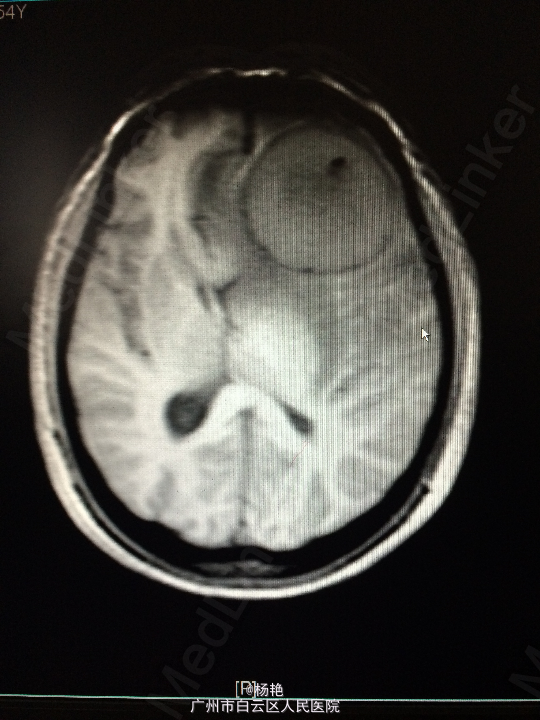

主诉:反复头痛2年加重1周 病史:患者诉两年前无明显诱因反复出现头晕头痛不适,近一周来症状加重,无恶心呕吐、无行走不稳、肢体乏力、意识障碍等。遂至当地医院诊治,行头颅CT、MR检查均提示颅内占位,良性可能性大,考虑脑膜瘤。今患者为求进一步治疗而入我院。

查体:神经系统查体未见明显异常 辅助检查:头颅MR提示:左侧额叶区域较大类圆形肿物,多考虑脑膜瘤可能;大脑前动脉及中动脉受压,中线偏移。

诊断:左额叶脑膜瘤 处理:在静脉全麻下行左侧额底脑膜瘤切除术,术后病理提示:脑膜瘤